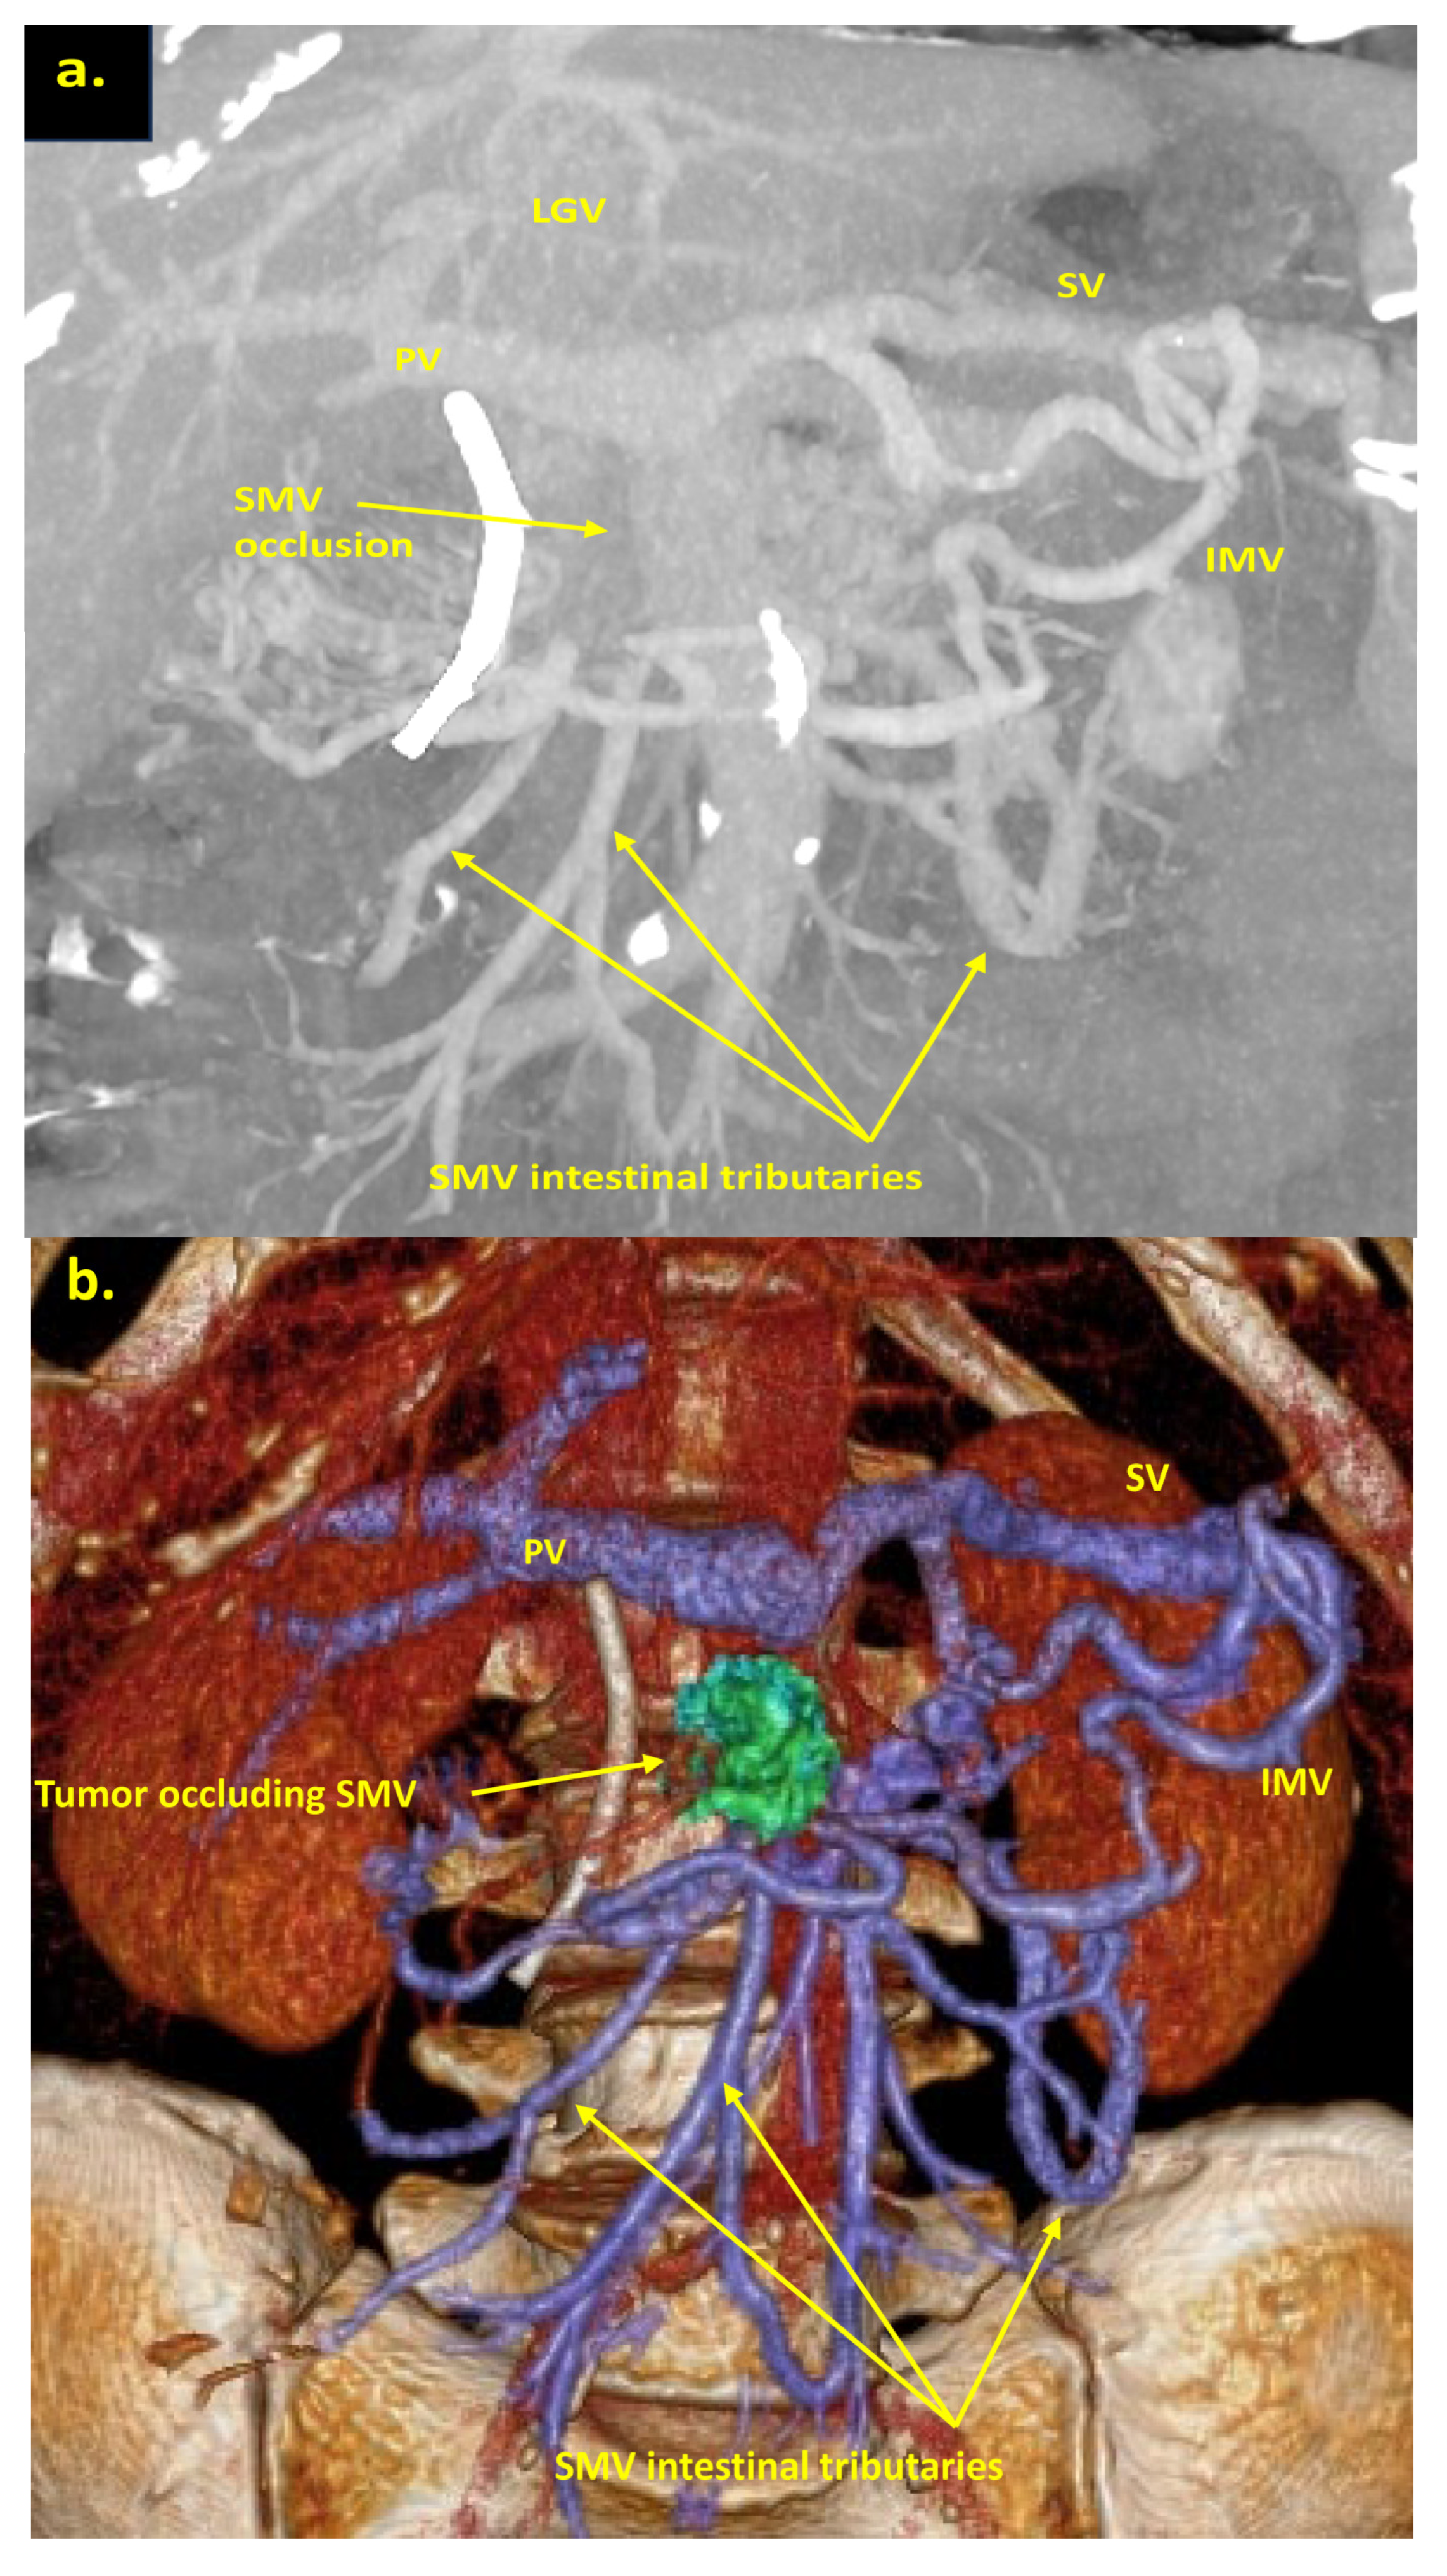

The combination of CT, MRI, PET/CT, and blood CA 19-9 was used as the best modality for the selection of candidates for radical surgery in patients with LA PDAC [11] by the evaluation of vascular involvement and distant metastases. Interpretation of the standardized digital images from the preoperative multiphase pancreatic MDCTs, MRIs, and PET/CTs (when available) of all 19 patients was independently performed by three abdominal image readers (PP, AD, EK). High-quality CT-based pancreatic protocol was the standard method of the anatomical resectability assessment with the analysis of four phases: native, arterial (pancreatic), portal venous, and delayed phases following high concentrated (350–400 mg/mL) non-ionic iodinated contrast media injection at the rate of 2.5–5.0 mL/s. CT examinations were performed between 2006 and 2024, using 32- to 256-detector scanners Philips Ingenuity, Philips iCT, GE optima CT 540, Philips Brilliance CT, Philips iCT, Toshiba Aqullion, and GE Revolution, with machine-specific image acquisition ranging from 0.625 to 3 mm axial slice thickness. Since 2008, 3D abdominal vein reconstructions have become useful and necessary components for decision-making on possible radical surgery for “low” pancreatic cancers with SMV thrombosis/involvement (Figure 1a–d). After ruling out the distant metastases, only patients with specific vein anatomy can be candidates for radical surgery. The mandatory anatomical conditions for the procedure were the following: (1) preserved SMV-SV confluence; (2) occluded SMV for any reason (tumor or thrombus); (3) well-developed inferior mesenteric vein (IMV) collaterals with dilated intestinal veins; (4) no right-sided vein collaterals (which will be sacrificed); and (5) no varices in the upper abdomen.

Figure 1.

Post-processing reconstructions of MDCT portal phase images for adenocarcinomas of the pancreatic uncinate process, associated with SMV occlusion, caused by its thrombosis and/or involvement. Three-dimensional maximum intensity projections (MIP) and volume-rendered (VR) imaging show preserved SMV-SV confluence, occluded SMV, well-developed IMV collaterals with dilated intestinal veins, and the absence of right-sided vein collaterals and varices. (a) Three-dimensional MIP reconstruction shows the dilated SMV tributaries, gastro-epiploic venous arcade (GEVA), left gastric (LGV), and inferior mesenteric veins (IMV) flowing into the splenic vein (SV); (b) three-dimensional MIP reconstruction. Dilated gastro-epiploic vein (GEV), and IMV anastomosing with the SV; (c) three-dimensional VR reconstruction. SMV is thrombosed and surrounded by the tumor; (d) three-dimensional VR reconstruction shows the dilated SMV tributaries and IMV flowing into the splenic vein (SV). The tumor shrank after chemotherapy, the SMV is occluded and the narrow left SMV is going along it. PV-portal vein. Abbreviations correspond to all the figures.

Pancreatoduodenectomy with the SMV and all its tributaries resection without reconstruction for the uncinate PDAC in 64-year-old male. On CT the tumor invades the SMV, which is occluded, the SMV-SV confluence is preserved, and the IMV collaterals are well-developed with dilated intestinal veins, without right-sided vein collaterals and varices. (a) Three-dimensional MIP and (b) three-dimensional VR reconstructions show the dilated SMV tributaries, gastro-epiploic venous arcade, and IMV flowing into the SV; (c) the picture of the operating field after the extended Whipple procedure with the SMV and all its tributaries resection without reconstruction. CHA—common hepatic artery, IVC—inferior vena cava.

Total pancreatectomy with the SMV and all its tributaries resection with resection of IMV and its transposition into SV stump, combined with SMA resection and reconstruction for the uncinate PDAC in 71-year-old female. On CT the tumor invades the IMV and SMV (the last one is occluded), the SMV-SV confluence is preserved, and the IMV collaterals are well-developed with dilated intestinal veins, without right-sided vein collaterals and varices. (a) Three-dimensional MIP and (b) three-dimensional VR reconstructions show the dilated intestinal veins flowing into the IMV, which connects to the SV; (c) the picture of the operating field after the extended Whipple procedure with the SMV and all its tributaries resection without reconstruction. CHA—common hepatic, LGA—left gastric, SA—splenic, RHA—right hepatic, LHA—left hepatic, SMA—superior mesenteric arteries, CA—celiac artery, IVC—inferior vena cava.

Pancreatoduodenectomy with the SMV and all its tributaries resection without reconstruction for the uncinate PDAC in 57-year-old female. On CT the tumor invades the SMV, which is occluded, the SMV-SV confluence is preserved, and the IMV collaterals are well-developed with dilated large collecting intestinal vein, without right-sided vein collaterals and varices. (a) Three-dimensional MIP and (b) three-dimensional VR reconstructions show the dilated large collecting intestinal vein flowing into the IMV, which connects to the SV; (c) the picture of the operating field after the extended Whipple procedure with the SMV and all its tributaries resection without reconstruction. CHA—common hepatic, LGA—left gastric, SA—splenic, SMA—superior mesenteric arteries, IVC—inferior vena cava; (d) the way of the intestinal blood flow after surgery.

We used different post-processing CT techniques for the assessment of the peripancreatic vessels and collateral venous blood flow adequacy, such as shaded surface display, maximum intensity projection, and 3D volume-rendered (VR) reconstruction imaging. Now, when planning SMV resection with excision of all its tributaries for “low” pancreatic cancer, we consider CT-based 3D-VR reconstruction the best and most necessary option for the depiction of the collateral venous system. Compared to the other rendering CT techniques, VR is superior in delineating vessels, pancreatic parenchyma, the tumor, and adjacent structures (Figure 1a–d, Figure 5a,b, Figure 6a,b and Figure 7a,b,d) [43,44,45].